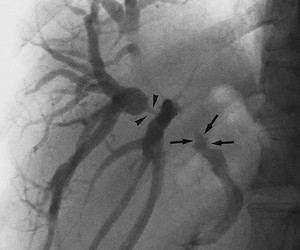

Colangiocarcinomul perihilar definește tumorile care se dezvoltă începând cu ductele biliare secundare până deasupra originii ductului cistic. Formele cu localizare hilară sunt numite și tumori Klatskin. Ca și forma intrahepatică, colangiocarcinomul perihilar poate fi exofitic (sub forma unei mase tumorale) sau cu pattern de creștere intraductal (nodular sau infiltrativ). Clinic apare icter indolor, colangită, scădere ponderală, anorexie. Biologic, CA 19-9 poate fi crescut. Pentru diagnostic și stadializare se efectuează ERCP, ecoendoscopie (EUS), CT și IRM (MRCP, magnetic resonance cholangiopancreatography). Clasificarea se face după sistemul Bismuth-Corlette (în funcție de segmentul de arbore biliar afectat) iar mai nou s-a propus un sistem extins care include și mărimea și morfologia tumorii, afectarea vasculară și limfatică, prezența metastazelor și bolile hepatice concomitente (Deoliveira ML et al). ERCP-ul permite realizarea unui diagnostic citologic prin periaj și poate avea și valoare terapeutică, prin dilatarea stricturilor sau plasarea unui stent pentru dezobstrucția căii biliare. Puncția fin aspirativă ecoendoscopică (EUS-FNA) nu trebuie efectuată decât atunci când diseminarea pe traiectului acului de puncție nu modifică managementul pacientului. Tratamentul constă în rezecție locală cu hepaticojejunoamastomoză pe ansă în Y a la Roux, transplant hepatic (eventual cu chimioradioterapie neoadjuvantă), chimioterapie sistemică.

Referințe: Classification, Diagnosis, and Management of Cholangiocarcinoma, Clinical Gastroenterology and Hepatology, foto: radiographics.rsna.org